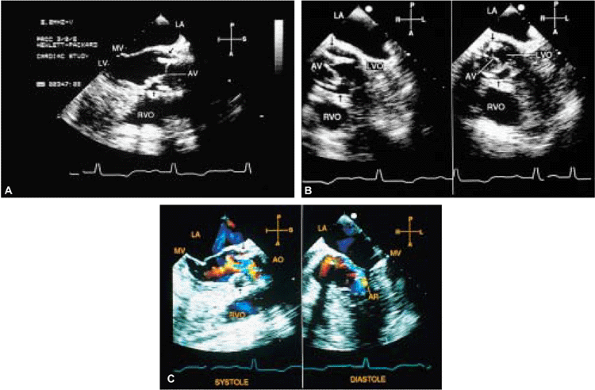

FIGURE 5.30. CarboMedics aortic prosthesis: normal. A. The prosthesis in the closed position in diastole (arrowhead). B. Both leaflets in the open position (arrow) in systole.C. The leaflets (arrowhead) are open in systole. The suture ring is also seen in C and in D and E (arrow). F,G. Two jets of normal mild aortic regurgitation (AR) (arrows) that are eccentrically located. LA, left atrium; AO, aorta; LV, left ventricle; RVOT, right ventricular outflow tract. |